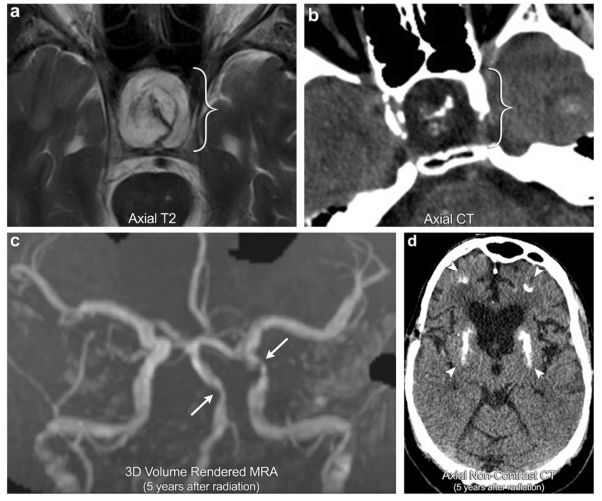

案例1:放射性血管病变和放射性矿化性微血管病

35岁男性,有放射史治疗颅咽管瘤的病史(括号)。病人随后几年连续进展出现多次卒中,MRA图像显示多个区域严重的颅内血管狭窄,较明显的是基底动脉和左侧床突上段颈内动脉(箭头);这与放射性血管病变相一致。CT显示皮层下的脑白质和基底节区(箭头所指)出现致密钙化,与矿化性微血管病变一致。